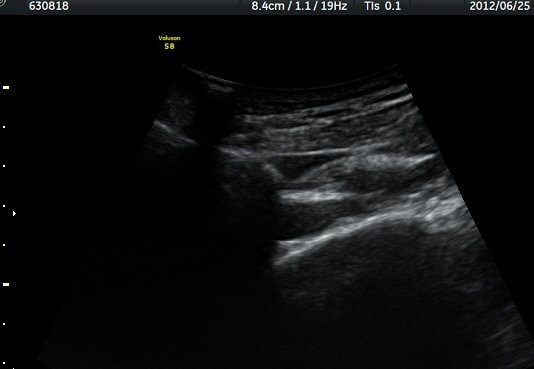

¾î±ú °üÀý µÚÂÊ ÈĹæ°üÀý¼ø Ⱦ´Ü¸é°Ë»ç¿¡¼­ °üÀý¼ø ³»Ãø, °¡½Ãµ¹±â°üÀý¼ø°í¶û(spinoglenoid

notch)¿¡¼­ Àú¿¡ÄÚ ³¶Á¾ÀÌ °üÂûµÈ´Ù(±×¸² 1). ŽÃËÀÚ¸¦ À§-¾Æ·¡ ¹æÇâÀ¸·Î º¯°æÇÏ¿© °üÂûÇÒ ¶§µµ

¿ª½Ã °ß°©°ñ °¡½Ãµ¹±â(spine) ¾Æ·¡¿¡¼­ Àú¿¡ÄÚ ³¶Á¾ÀÌ °üÂûµÈ´Ù(±×¸² 2). º¼·ÏŽÃËÀÚ·Î ¹Ù²Ù¾î °ü

ÂûÇÏ´Ï  °¡½Ãµ¹±â°üÀý¼ø°í¶û¿¡¼­ Àú¿¡ÄÚ ³¶Á¾ÀÌ ´õ¿í ¶Ñ·ÈÈ÷ °üÂûµÈ´Ù(±×¸² 3, 4).